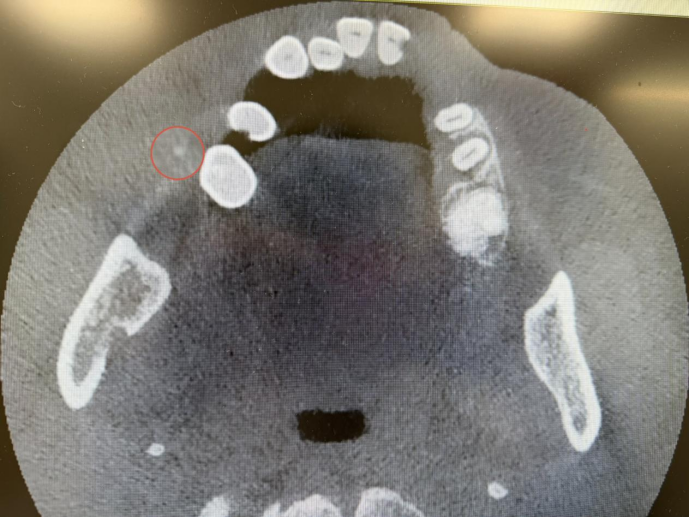

口腔科主任刘超接诊后迅速完善检查,明确诊断为右侧腮腺区导管结石。传统手术需要全身麻醉切除腮腺体,创伤较大。但患者高龄,且有明确心梗病史,术前检查提示心率过慢,全身麻醉可能诱发心源性意外,手术风险极高,常规方案根本无法实施。

面对德州地区尚无先例的技术空白,以及常规手术无法开展的棘手状况,刘超在全面、严谨评估患者情况后,决定采用内镜微创取石术,并大胆选择局部麻醉方案,以最大限度规避心源性风险、减轻患者负担。

在无先例、高风险、强压力的情况下,刘超凭借深厚的专业功底、丰富的临床经验与精湛娴熟的技艺成功在内镜下完整取出结石,全程未损伤任何重要神经血管,圆满完成了这例区域内开创性的高难度微创手术。